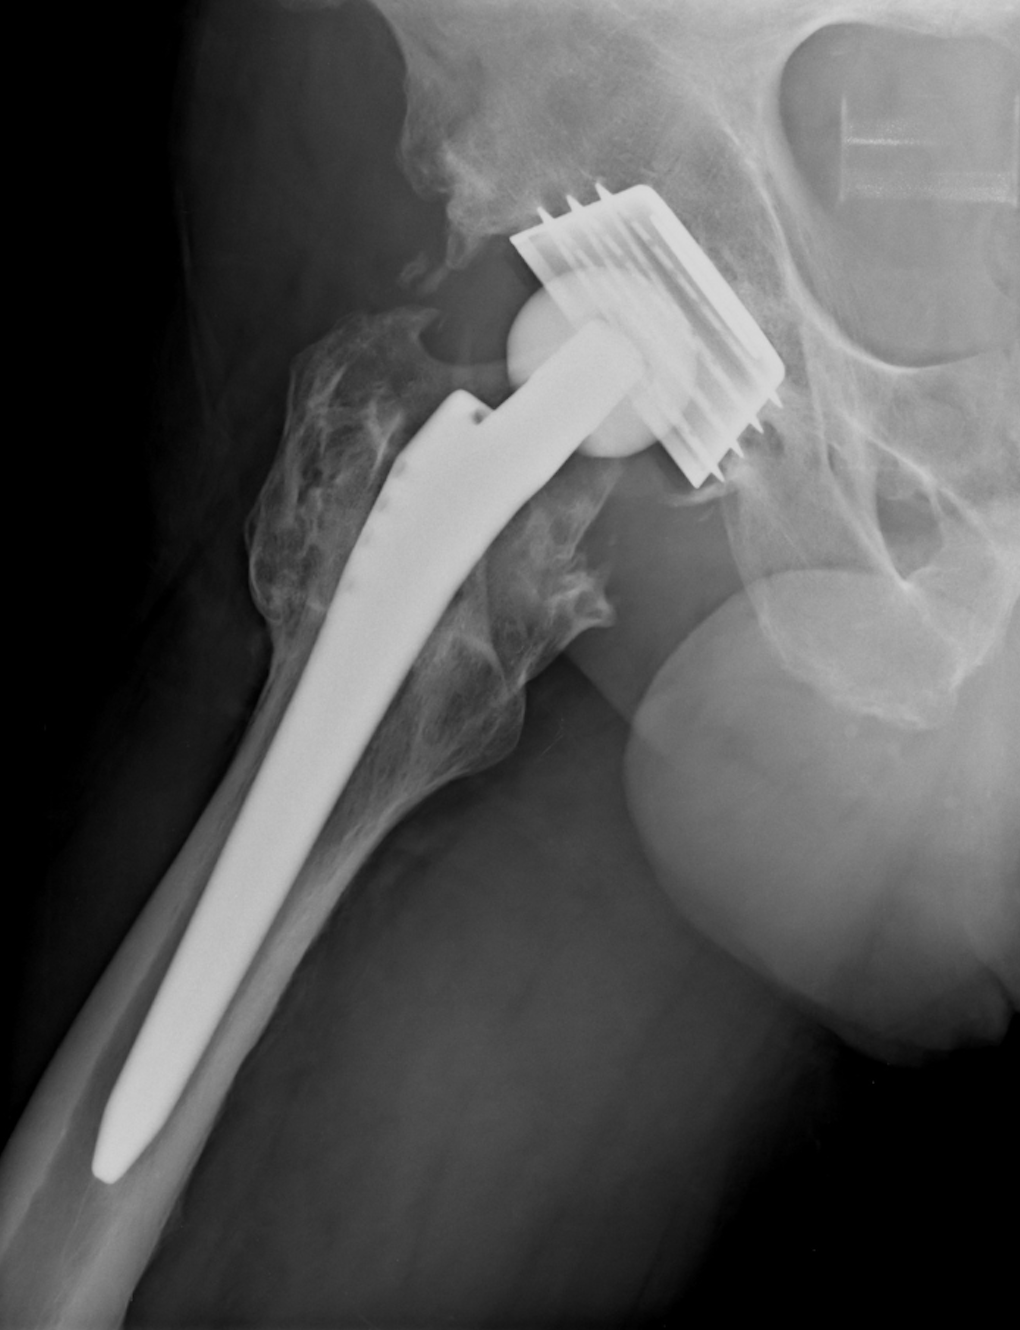

Revision Hip & Knee Clinic

Are you having problems with your joint replacement? Whether it’s worn out or has just never been right, we offer a comprehensive consultation and assessment to establish the right diagnosis. Our surgeons are experts in hip and knee replacement and can advise you on treatment options specific to your individual case. Get in touch, we are here to help.